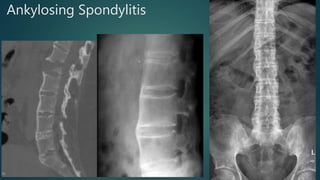

Ankylosing Spondylitis

• #77 1.chalk stick fracture-Single sagittal image of the lumbar spine demonstrates a fracture extending from the anterior disc margin, through the inferior body of L1 and through the posterior elements. Note extensive syndesmophytic fusion of the discs spaces and posterior elements consistent with ankylosing spondylitis. 2.Typical features of ankylosing spondylitis with syndesmophytes, bamboo spine and bony fusion of posterior elements (dagger sign). 3.Throughout the spine, the vertebral bodies are fused by marginal syndesmophytes giving the appearance of Bamboo spine.